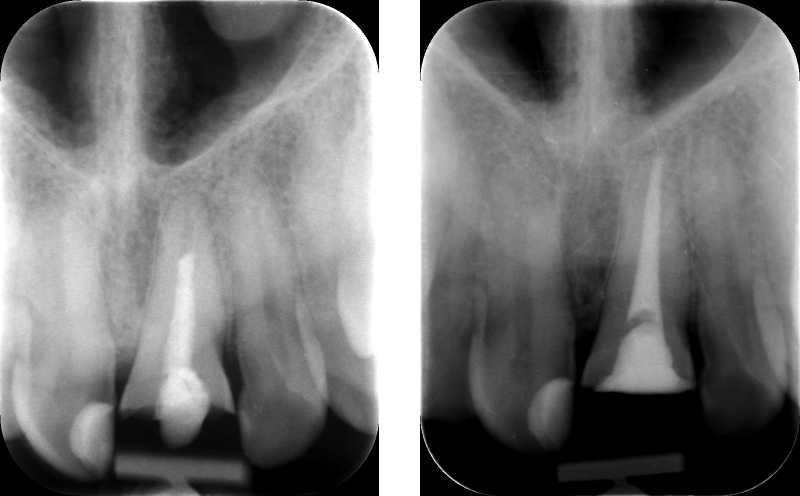

Az első feladatunk a régi gyökértömés cseréje volt, amihez gépi gyökércsatorna-tágítót és elektromos gyökércsatorna-bemérő műszert is használtunk.

A régi gyökértömés cseréje